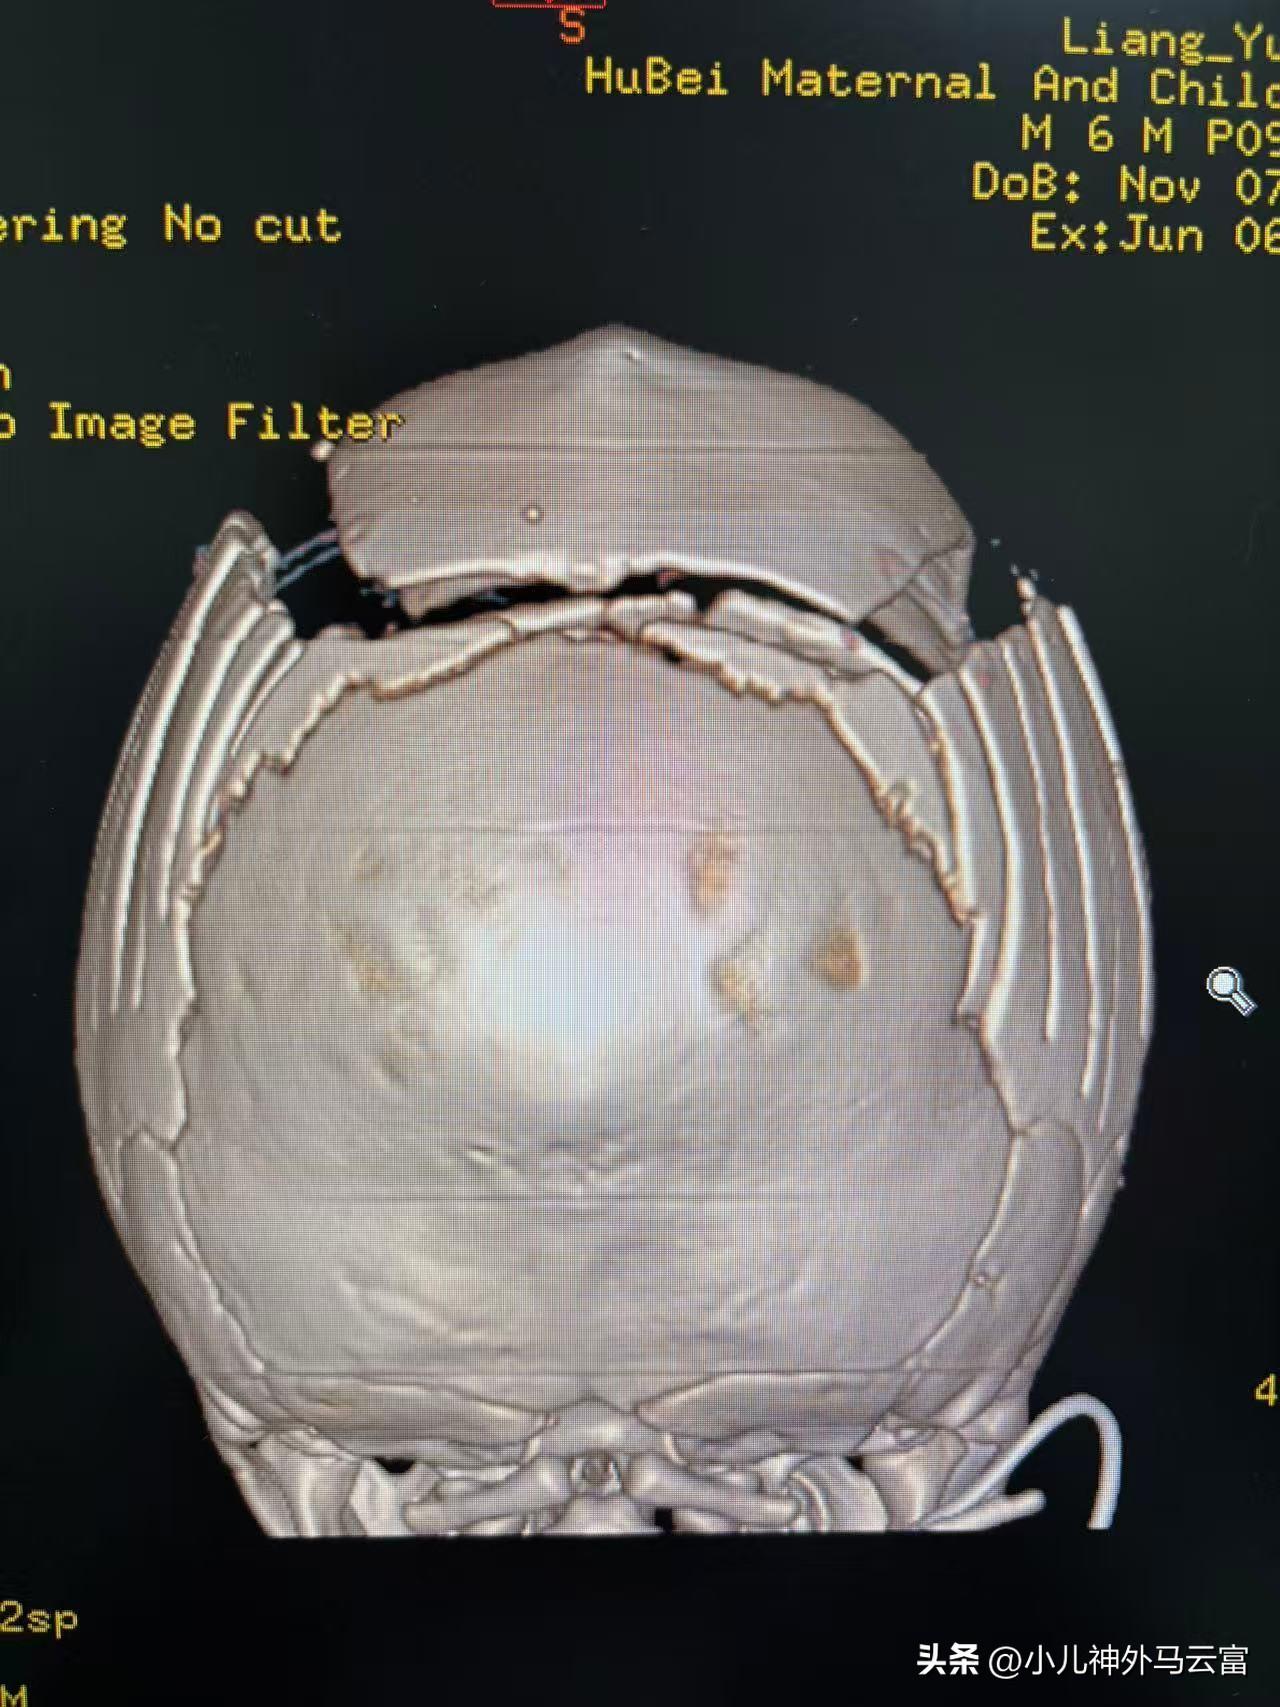

【基本信息】男,6個月28天

【疾病類型】顱縫早閉(矢狀縫),舟狀頭

術前影像、照片: